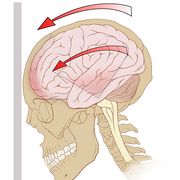

脑动脉瘤是颅内动脉血管的异常瘤状突起。脑动脉瘤不破裂,一般病人没有明显症状,如果破裂出血,常表现为蛛网膜下腔出血,病人可以出现剧烈的头痛,恶心呕吐,甚至出现...11216人收听

- 脑动脉瘤相关知识脑动脉瘤简单说就是脑动脉血管壁上膨出的血管泡,血管泡在血液不间断的冲击下,就象吹气球一样,球吹得越大,血管壁就变得越薄,血管也就越容易破裂。一般认为